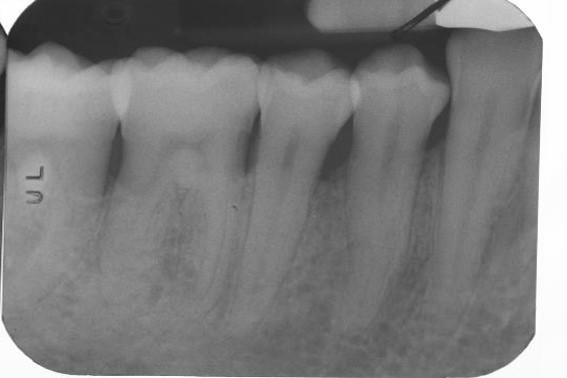

17/22 - Radiographic follow up 12 months post-operative. The radiograph demonstrates a complete defect fill and a stable result.

Deep intrabony defects treated using Straumann® Emdogain® - Dr. M. Stefanini